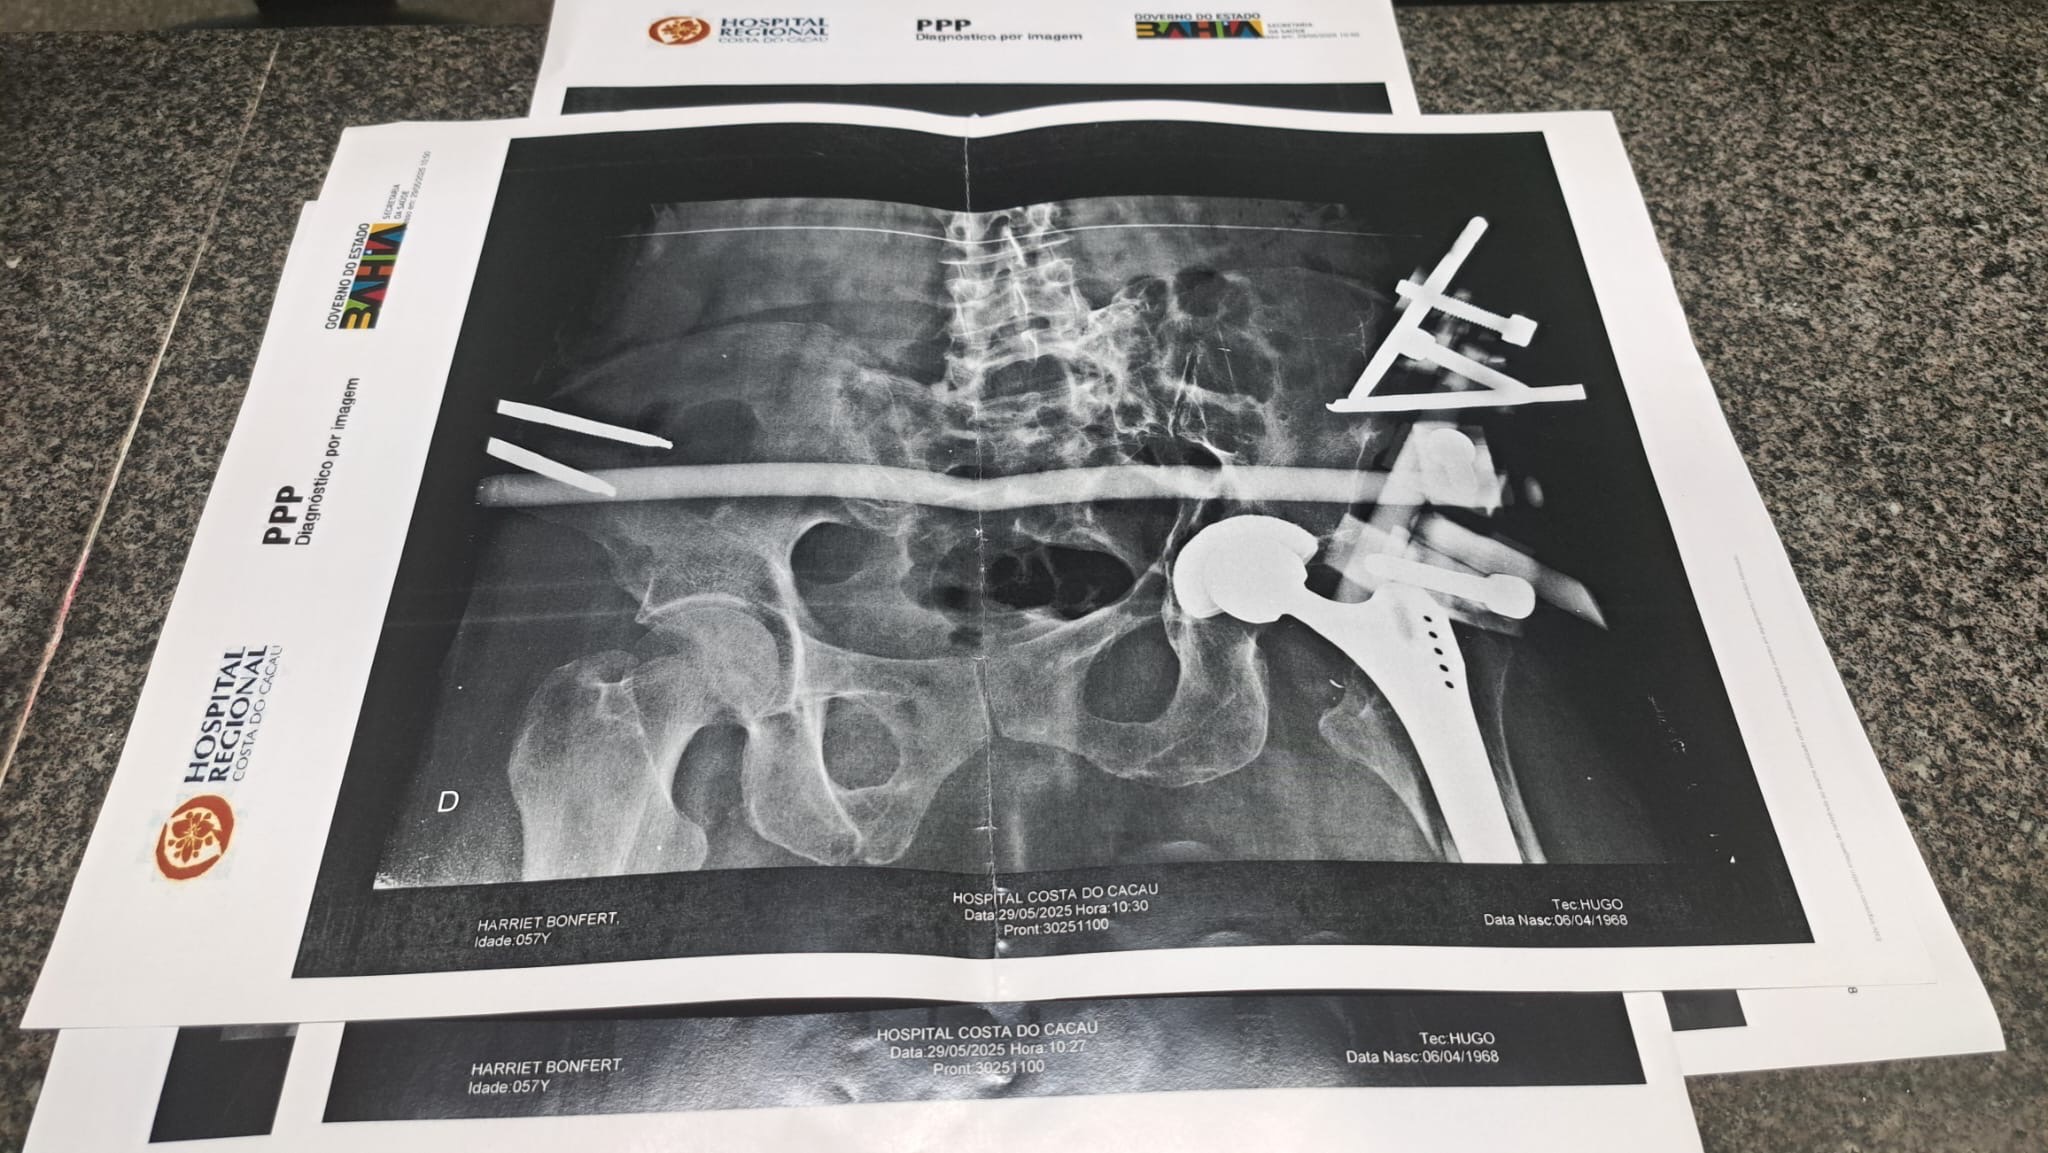

Unsere liebe Freundin Harriet wurde in Brasilien von einem Auto angefahren – ein tragischer Unfall, der ihr Leben von einem Moment auf den nächsten völlig verändert hat. Sie erlitt dabei 14 Knochenbrüche, verteilt über ihren gesamten Körper.

Seitdem liegt sie im Krankenhaus, mit unzähligen Schrauben und Metallstangen im Körper, voller Schmerzen. Die medizinischen Bedingungen vor Ort sind katastrophal, und die behandelnden Ärzte haben ihr gesagt, dass sie nichts mehr für sie tun können.